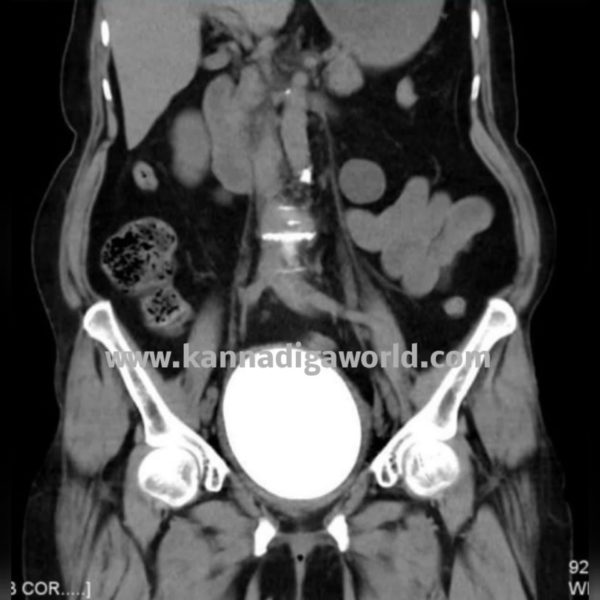

60 ವರ್ಷ ವಯಸ್ಸಿನ ಮಹಿಳೆ ಕಳೆದ ಆರು ವರ್ಷಗಳಿಂದ ಉರಿ ಮೂತ್ರ ದೂರುಗಳೊಂದಿಗೆ ಸ್ಥಳೀಯ ಆಸ್ಪತ್ರೆಗೆ ಭೇಟಿ ನೀಡುತ್ತಿದ್ದರು. ಈ ರೋಗಲಕ್ಷಣಗಳ ಪ್ರತಿ ಭೇಟಿಯಲ್ಲಿ ಮೂತ್ರನಾಳದ ಸೋಂಕಿಗೆ ಪ್ರಾಯೋಗಿಕವಾಗಿ ಚಿಕಿತ್ಸೆ ನೀಡಲಾಗಿತ್ತು. ಇತ್ತೀಚೆಗೆ ಕಸ್ತೂರ್ಬಾ ವೈದ್ಯಕೀಯ ಕಾಲೇಜು ಮತ್ತು ಆಸ್ಪತ್ರೆಗೆ ಭೇಟಿ ನೀಡಿದ್ದರು. ರೋಗಿಗೆ ಸರಳ ಸಿಟಿ ಸ್ಕ್ಯಾನ್ ಮಾಡಲಾಗಿದ್ದು ಇದರಿಂದ ಸಂಪೂರ್ಣ ಮೂತ್ರಕೋಶವನ್ನು ಆಕ್ರಮಿಸಿಕೊಂಡಿರುವ ಗಮನಾರ್ಹವಾದ ವಸ್ತು ಇರುವುದನ್ನು ಬಹಿರಂಗಪಡಿಸಿತು.

ಮೂತ್ರಶಾಸ್ತ್ರ ವಿಭಾಗದ ಪ್ರಾಧ್ಯಾಪಕ ಮತ್ತು ಉಪ ವೈದ್ಯಕೀಯ ಅಧೀಕ್ಷಕರಾದ ಡಾ.ಪದ್ಮರಾಜ್ ಹೆಗ್ಡೆ ಅವರ ಮಾರ್ಗದರ್ಶನದಲ್ಲಿ 11.5 x 7.5 ಸೆಂ.ಮೀ ಅಳತೆಯ 672 ಗ್ರಾಂ ತೂಕದ ಮೂತ್ರಕೋಶದ ಕಲ್ಲನ್ನು ಡಾ.ಅಾಂಶುಮನ್, ಡಾ.ಕಾಶಿ ವಿಶ್ವನಾಥ್, ಡಾ.ನಿಶಾ ಡಾ ವಿವೇಕ್ ಪೈ ಮತ್ತು ಡಾ ಕೃಷ್ಣ ಅವರ ತಂಡವು ತೆರೆದ ಸಿಸ್ಟೊಲಿಥೊಟಮಿ ಶಸ್ತ್ರಚಿಕಿತ್ಸೆ ಮೂಲಕ ಹೊರ ತೆಗೆದರು. ಎರಡನೇ ದಿನ ರೋಗಿಯನ್ನು ಆಸ್ಪತ್ರೆಯಿಂದ ಬಿಡುಗಡೆ ಮಾಡಲಾಯಿತು.

ಅಲ್ಟ್ರಾಸೋನೋಗ್ರಫಿ ಅಥವಾ ಎಕ್ಸ್-ರೇನಂತಹ ಆರೋಗ್ಯ ಸೌಲಭ್ಯಗಳನ್ನು ಹೊಂದಿರುವ ಗ್ರಾಮೀಣ ಪ್ರದೇಶಗಳಲ್ಲಿ ರೋಗನಿರ್ಣಯವನ್ನು ಮಾಡುವುದು ಸವಾಲಿನ ಸಂಗತಿಯಾಗಿದೆ. ನಮ್ಮ ಜ್ಞಾನದ ಪ್ರಕಾರ ಆರೋಗ್ಯವಂತ ವಯಸ್ಕ ಮಹಿಳೆಯಲ್ಲಿ 672 ಗ್ರಾಂ ತೂಕದ ದೈತ್ಯ ಮೂತ್ರಕೋಶದ ಕಲ್ಲು ಪ್ರಕರಣವು, ನಮ್ಮ ಜ್ಞಾನದ ಪ್ರಕಾರ ಇದು ವಿಶ್ವದಲ್ಲಿ ವರದಿಯಾಗಿರುವ ಮಹಿಳಾ ರೋಗಿಯಲ್ಲಿನ ಅತಿ ದೊಡ್ಡ ಮೂತ್ರಕೋಶದ ಕಲ್ಲು. ಇಲ್ಲಿಯವರೆಗೆ ವರದಿಯಾದ ಅತಿದೊಡ್ಡ ಮೂತ್ರಕೋಶದ ಕಲ್ಲು ಮುಂಬೈನ ಕೆಇಎಂ ಆಸ್ಪತ್ರೆಯಿಂದ, ಅದು 528 ಗ್ರಾಂ ತೂಕವಿತ್ತು.